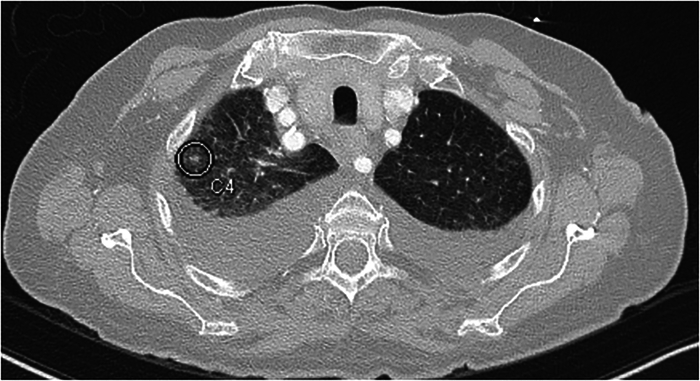

Purpose: Computed tomography angiography (CTA) of the head and neck includes the pulmonary apices, a common location for pulmonary nodules. Computer-aided detection (CAD) is an adjunctive tool for the detection of lung nodules and is widely used in standard chest CT scans. We evaluated whether the available software can be applied to CTA head and neck examinations, which include the lung apices, resulting in improved accuracy for lung nodule detection.

Materials and methods: In this retrospective single-center study, 191 previously reported head and neck CTA scans were re-evaluated for apical pulmonary nodules by 2 radiologists. Subsequently, CAD software ( Syngo .via, Siemens Healthiness AG) was applied to the lung apices and the results were compared between CAD and research radiologists (first reading) or clinical radiologist (null reading). In addition, the CAD performance in limited lung fields was compared with the accepted CAD assessment applied to whole lungs.

Results: Of the 191 patients, 110 (57.6%) were men, with a mean age of 68 years. In the 24 CT scans, the research radiologists detected 40 nodules. In the 180 scans evaluated by CAD, the software detected 39 nodules in 22 examinations, with a sensitivity of 60.8% and a PPV of 63.6%. In the remaining 158 examinations in which CAD did not detect nodules, the radiologists concurred in 149 scans, with a specificity of 94.9%, NPV of 94.3%, and accuracy of 90.6%.

Conclusion: The study results indicate that CAD is an unexpected quick supportive tool for nodule detection, particularly for excluding clinically significant nodules in lung apices on CTA head and neck, showing similar results for partial and full lung fields.